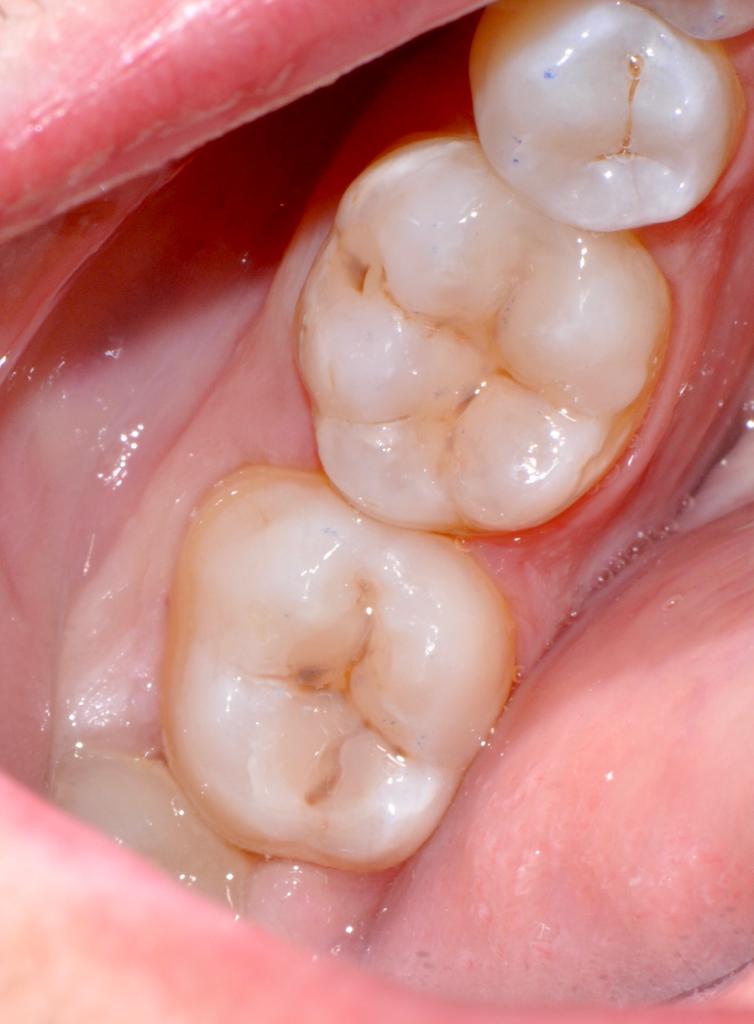

Alcuni casi clinici